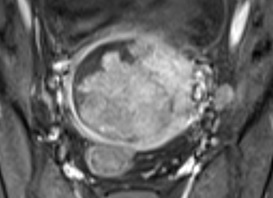

Ung thư biểu mô tuyến sợi tử cung (Uterine carcinosarcoma-UCS) là một loại ung thư phát triển trong tử cung